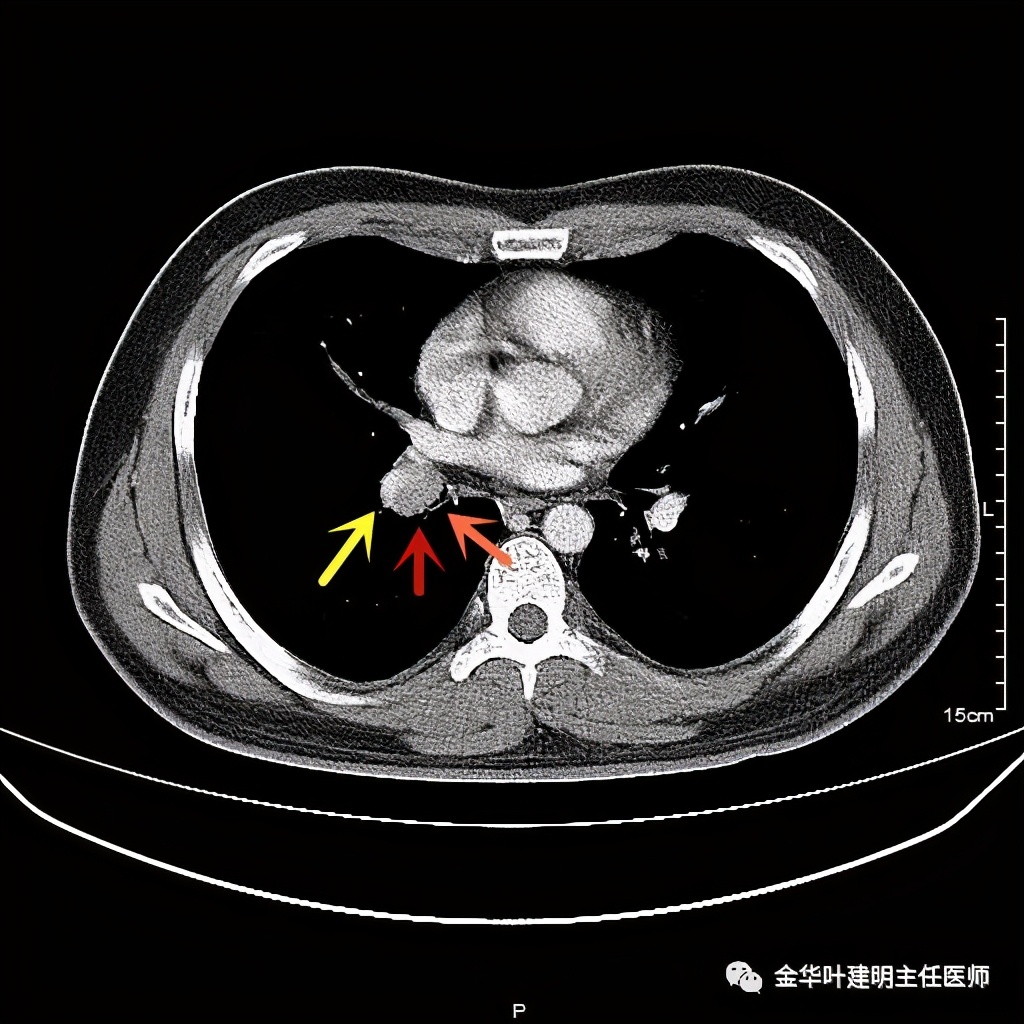

六、神经内分泌癌(此例为不典型类癌,小细胞癌以后再总结):

影像特征:不典型类癌一般圆形生长,实性,边缘比较光滑,但硬度不够。侵蚀力也不够。就像这例,我们发现其与肺动脉接触的地方,居然无法推压血管,反而肿瘤被血管占据了其生长的位置,在支气管内,肿瘤也是对支气管壁没有造成明显的破坏。也就是说 圆形边清较软、侵蚀力弱的实性结节 要考虑类癌的可能性。